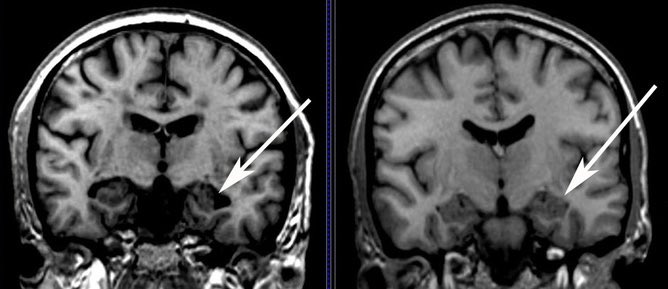

4️⃣ صِغَر حجم بعض أجزاء الدماغ، على سبيل المثال

smaller hippocampal volume